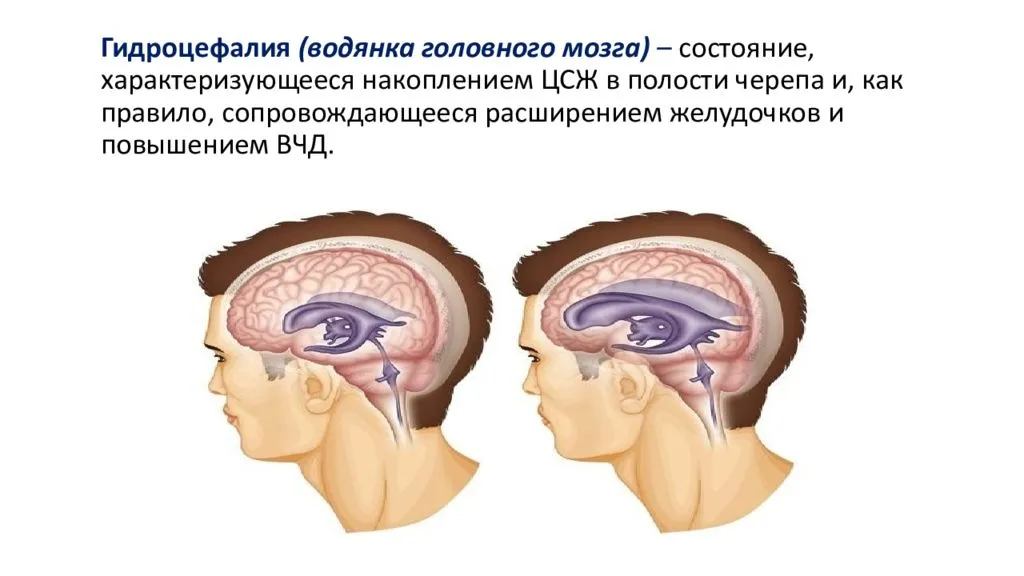

Признаки умеренно выраженной наружная

Признаки умеренно выраженной наружная 113 фото